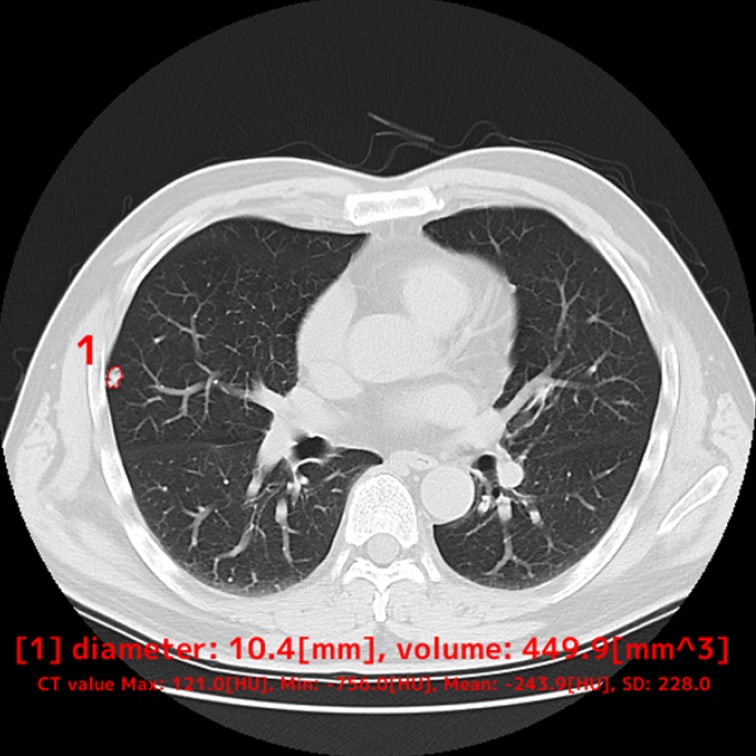

以下の肺結節候補領域を検出して表示します- 充実型:3mm以上30mm以下

- 部分充実型:5mm以上30mm以下

- すりガラス型:5mm以上30mm以下

- 自動計測

- 検出した候補領域の大きさ:体積 [mm³] およびAxial断面最大径 [mm] を出力

- CT値:最大・最小・平均値・標準偏差を出力

解析事例

低線量CT

* 低線量CTについて

通常のCTに比べ、被検査者に与える被ばく量を軽減することが可能です。一方、撮影される画像は、通常のCTに比べて質が低下する傾向にあり、読影診断の難易度が高まると言われています。